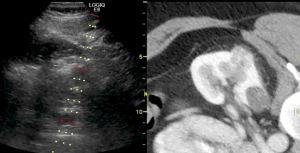

Our section performs and interprets the entire gamut of advanced diagnostic abdominal and pelvic imaging across multiple modalities, including computed tomography (CT), magnetic resonance imaging (MRI), ultrasound, radiography, and fluoroscopy. Our protocols are all encompassing and wide-ranging, including both common and organ-specific complex indications for medical imaging. This includes complete oncologic diagnosis and staging, inflammatory bowel disease, trauma evaluation, emergency radiology, transplant evaluations (such as liver, kidney, pancreas, and bowel), post-operative assessment, genitourinary and reproductive imaging, placental and fetal imaging, CT colonography, contrast enhanced ultrasound, and 3D imaging.

We also perform numerous interventional procedures across the entire body including image-guided minimally invasive biopsies of major solid organs. We have a robust solid organ and soft tissue ablation program with expertise in a wide variety of techniques including microwave ablation, radiofrequency ablation, cryoablation, ethanol ablation, and histotripsy. We also perform fluid aspirations and drainages, including thoracentesis and paracentesis.